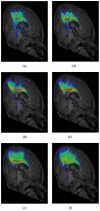

White matter fiber tractography plays a key role in the in vivo understanding of brain circuitry. For tract-based comparison of a population of images, a common approach is to first generate an atlas by averaging, after spatial normalization, all images in the population, and then perform tractography using the constructed atlas. The reconstructed fiber trajectories form a common geometry onto which diffusion properties of each individual subject can be projected based on the corresponding locations in the subject native space. However, in the case of high angular resolution diffusion imaging (HARDI), where modeling fiber crossings is an important goal, the above-mentioned averaging method for generating an atlas results in significant error in the estimation of local fiber orientations and causes a major loss of fiber crossings. These limitatitons have significant impact on the accuracy of the reconstructed fiber trajectories and jeopardize subsequent tract-based analysis. As a remedy, we present in this paper a more effective means of performing tractography at a population level. Our method entails determining a bipolar Watson distribution at each voxel location based on information given by all images in the population, giving us not only the local principal orientations of the fiber pathways, but also confidence levels of how reliable these orientations are across subjects. The distribution field is then fed as an input to a probabilistic tractography framework for reconstructing a set of fiber trajectories that are consistent across all images in the population. We observe that the proposed method, called PopTract, results in significantly better preservation of fiber crossings, and hence yields better trajectory reconstruction in the atlas space.